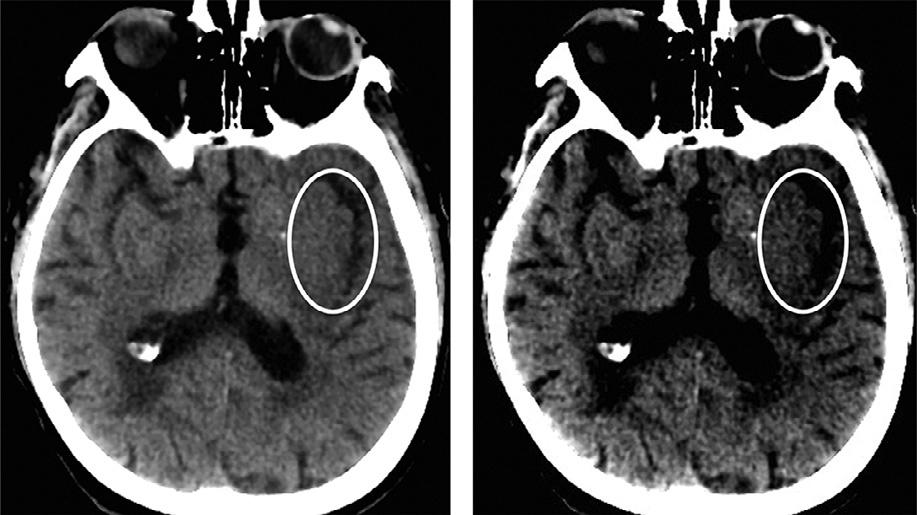

AclassicearlyischemicCTsignisfocalcorticalswelling.OtherearlyCTimagingsignsofstrokeinclude obscurationofthelentiformnucleusandinsularribbon (Fig.1.13)sign,bothattributabletolossofgray/whitematterdifferentiationwithhypodensityrelatedtovasogenicedema(Tomuraetal.,1988;Truwitetal.,1990). Thedetectionoftheseearlystrokesignsvariesbetween observers,buttheyaretypicallyseeninlessthantwothirdsofpatientsimagedat3hourspoststrokeonset. Parenchymalhypoattenuationisrelatedtoincreased watercontentfromvasogenicedemaandappearsto

Fig.1.13. Hypoattenuationoftheleftinsularribbon,anearly ischemiccomputedtomographysignofstroke,bettervisualized withnarrowwindowwidthdisplaysettings(35HU,right),than atstandardwindowwidthdisplaysettings(70HU,left).

beasignofirreversibletissueinjury,whilerecentstudies suggestthatfocalswellingalonemaybereversible. A10%increaseintissuewatercorrespondstoa20–30 HUdecreaseintissuedensity.